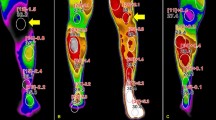

After LSB treatment of all subjects, the overall NRS score of CRPS patients significantly decreased, the SSR latency of the affected limbs was significantly shortened, and the SSR amplitude of the affected limbs was significantly increased (P < 0.05) (Fig. 3).

In CRPS patients before and after treatment, between the LSB (−) and LSB (+) groups, there was no significant difference in the change in SSR latency (103.98 ± 79.07 ms and 122.33 ± 91.34 ms) (P = 0.290); however, there was a significant difference in the change in SSR amplitude (54.73 ± 41.18 and 145.58 ± 61.81 µV) (P = 0.000) (Fig. 4).

There are very few articles investigating the role of SSR in CRPS diagnosis and treatment. In one study [26], CRPS patients showed prolonged latency of SSR. In another study [27], it was found that the mean amplitude was higher on the affected side, while the mean latency was shortened. However, after sympathetic block, amplitude was reduced, and latency was prolonged. The two studies had contradictory results, most likely because they were all restricted by a small number of patients. Lee et al. [28]. compared the results of sympathetic blocks to those of 263 people who had completed combined autonomic nervous system (ANS) testing to identify CRPS. Although the incidences of abnormal SSR tests were not substantial, they were considerably higher in the CRPS group. However, this study did not conduct quantitative stratification of SSR parameters and instead filtered out SSR-positive patients. As the pathogenic mechanism of the sympathetic nerve in CRPS has become more apparent in recent years [29], the application of sympathetic block treatment has increased again. As a result, choosing the most appropriate patients for individualized treatment is essential. According to our findings, following LSB to alleviate pain, the mean SSR amplitude increased, and the mean SSR latency shortened on the affected side (Fig. 3). These findings support LSB's effective treatment of pain symptoms in CRPS patients and clarify the range of changes in SSR parameters.

The reasons for the clinical positive response to LSB are multifaceted. Our results showed a significant difference in the change in SSR amplitude between the LSB (−) and LSB (+) groups before and after treatment. The effectiveness of LSB could potentially be predicted by changes in SSR amplitude (Fig. 4). Therefore, we analyzed age, BMI, sex, disease duration, baseline NRS, baseline SSR latency and amplitude. In accordance with previous research [36] on predictors, our results show that disease duration appears to be a factor determining the success of LSB, with patients having less than 12 months exhibiting a fourfold higher efficiency than patients with a longer duration. This indicates that CRPS with a duration ≥ 12 months is a poor prognostic factor for successful LSB treatment. Patients with CRPS may develop central sensitization, which can explain why sympathetic block is less effective over time [37]. SSR is thought to be triggered by synchronized sweat gland activity. The afferent part of the SSR is composed of large myelinated peripheral sensory fibers, whereas the efferent part is composed of sympathetic postganglionic unmyelinated C fibers that terminate in sweat glands. SSR is considered to be altered in CRPS due to increased sympathetic activity (4). In our results, an SSR amplitude < 510 µV was a good prognostic factor for successful LSB treatment.